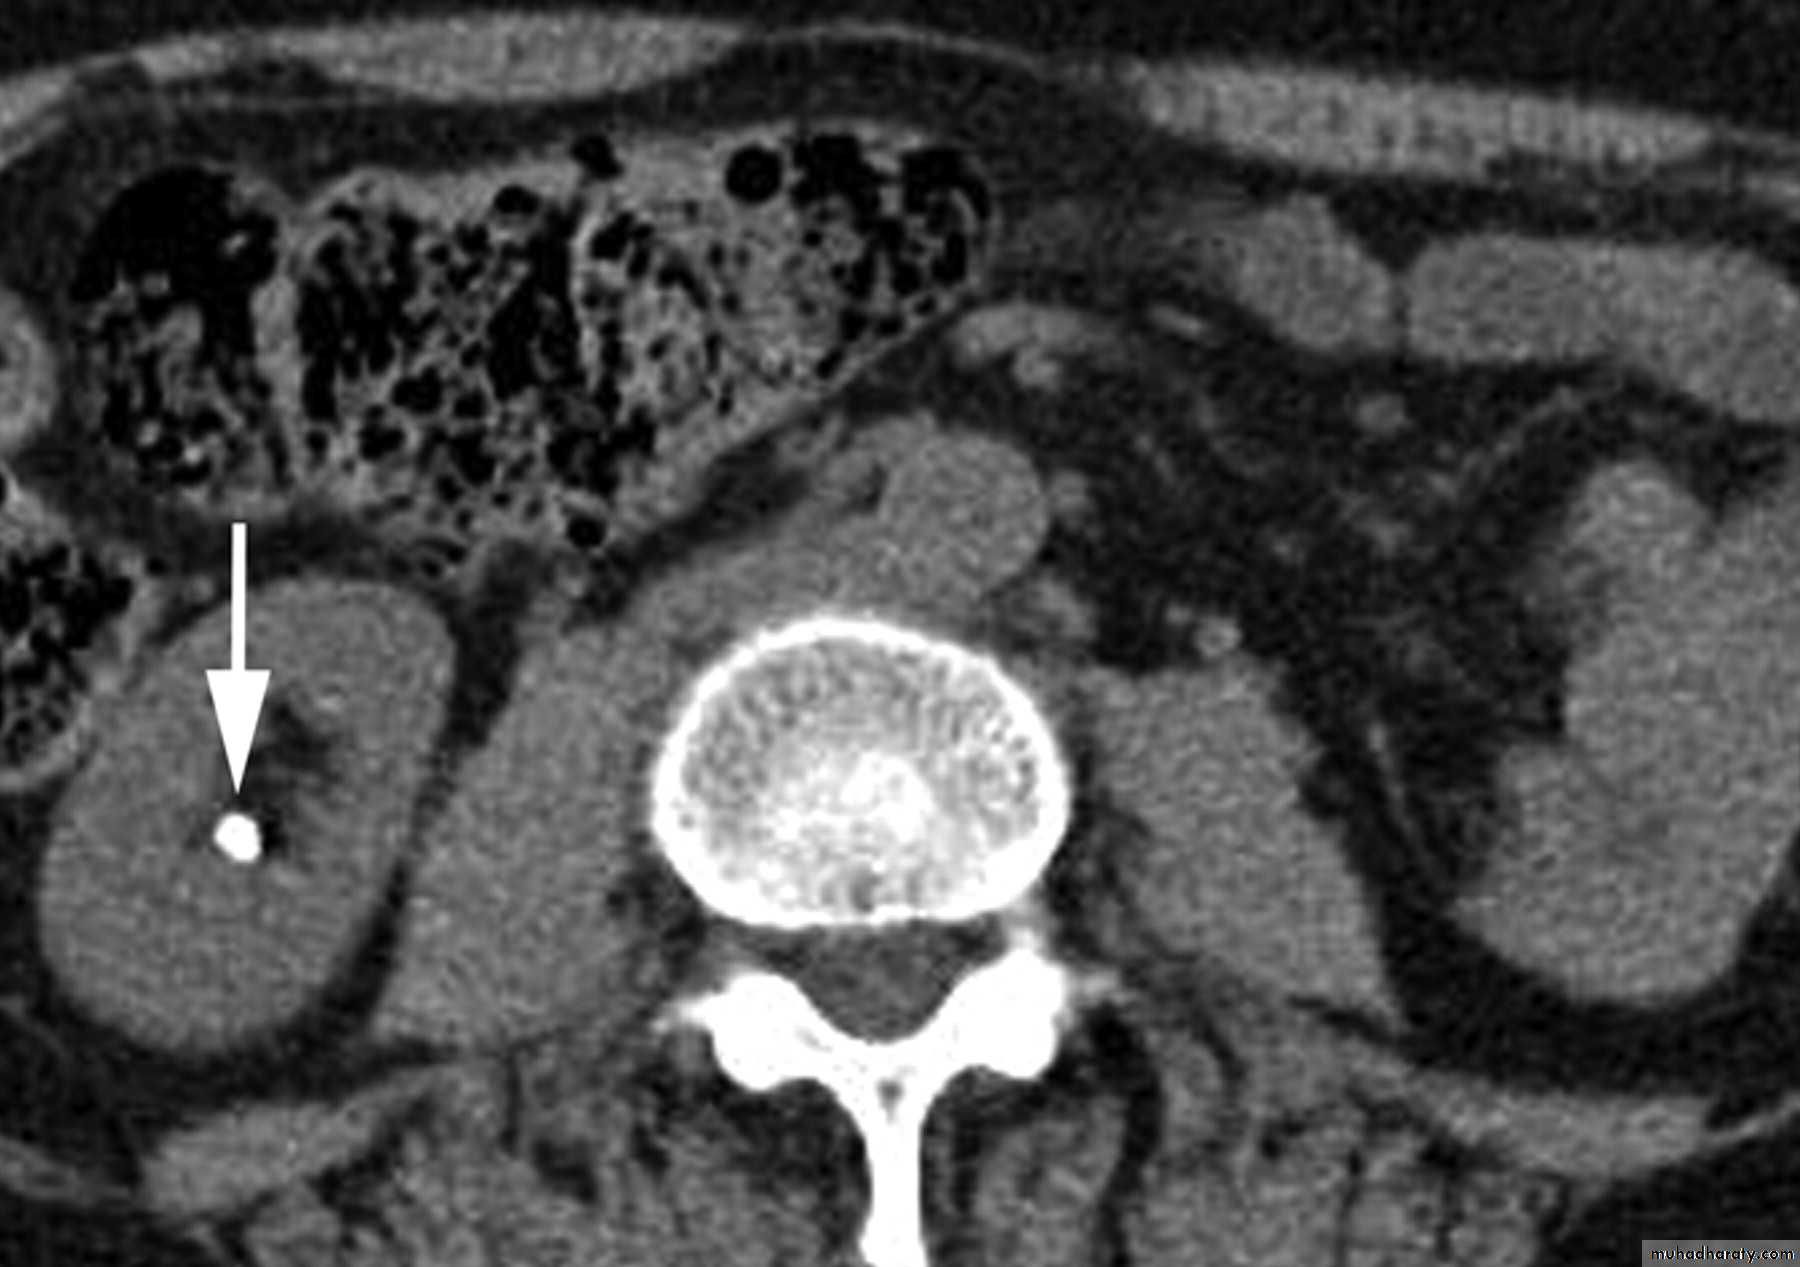

-Over 90% of calculi are radiopaque on plain films and virtually all on CT as very sensitive for detection of calculi, even those that appear radiolucent on plain film.-Most of these stones are a mixture of calcium oxalate and phosphate.

-Only pure uric acid and xanthine stones are radiolucent on plain x-ray but CAN be identified by CT or US, uric acid stones are associated with increased uric acid excretion in urine as in gout.

CT scans used in some hospitals during acute renal stone-Non contrast CT sensitively identify calculi and non opacified collecting system down to the level of obstruction. it has a sensitivity of 97% and specificity of 96% for detection of ureteral calculi